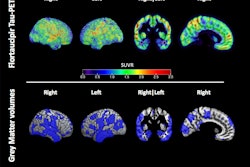

Thus, in this study, the researchers noted that they used the only biomarker of neurofibrillary tangles approved for clinical use by the U.S. Food and Drug Administration (FDA) and the European Medicines Agency (EMA), namely the imaging agent flortaucipir (Tauvid, Eli Lilly).

According to the analysis, out of 3,487 cognitively unimpaired participants, 349 (9.8%) were tau PET positive. The estimated frequency of tau PET positivity was less than 1% in those younger than 50, and increased from 3% at 60 years old to 19% at 90 years old. Tau PET positivity frequency increased across mild cognitive impairment (MCI) by 43% and AD dementia by 79% at 75 years old.

In addition, most tau PET-positive individuals (92%) were also amyloid PET-positive. Cognitively unimpaired participants who were positive for both amyloid PET and tau PET had a 57% risk of progression to MCI or dementia over the following five years compared with both amyloid PET-positive/tau PET-negative (17%) and amyloid PET-negative/tau PET-negative (6%) individuals.

Finally, among participants with MCI at the time of the tau PET scan, an amyloid PET-positive/tau PET-positive profile was associated with a 70% absolute risk of progression to dementia after five years, the researchers reported.